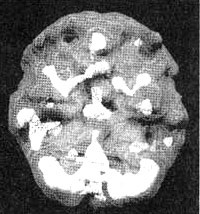

Когда Линда пришла ко мне на прием, ей было 26 лет. Два раза она подвергалась жестокому изнасилованию, ее любовник был садистом, а сама она подростком пережила смерть многих своих друзей. Она страдала от депрессии, тревоги, беспокойства и наркотической зависимости. На первом сканировании SPECT мы обнаружили повышенную активность поясной системы (трудности с переключением внимания), базальных ганглиев (тревога) и лимбической области (депрессии и неконтролируемые настроения). После четырех сеансов с использованием техники десенсибилизации и коррекции переработки информации с помощью движений глазных яблок (EMDR) — специального метода коррекции, применяемого для лечения после травмирующих событий, и одного месяца приема зверобоя (по 900 мг в день), Линда почувствовала себя значительно лучше. Повторное сканирование выявило нормализацию активности во всех.

Мозг Линды. Результаты сканирования SPECT

Трехмерное изображение — активный мозг, вид сбоку.

До лечения: обратите внимание на выраженное усиление активности в поясной системе, в базальных ганглиях и в лимбической системе.

После лечение зверобоем. Активность в поясной системе, в базальных ганглиях и в лимбической системе нормализовалась.

Трехмерное изображение — активный мозг, вид снизу.